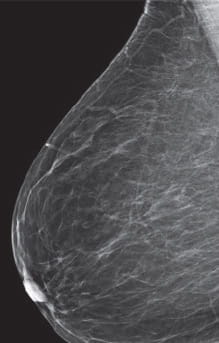

Radiologists classify breast density using a four-level density scale, as determined by a mammogram:

- Category A: Almost entirely fatty

- Category B: Scattered areas of dense breast tissue

- Category C: Heterogeneously dense

- Category D: Extremely dense

Having dense breast tissue may increase your chance of getting breast cancer. Dense breasts also make it more difficult for doctors to spot cancer on mammograms. Dense tissue appears white on a mammogram; lumps, both benign and cancerous, also appear white. So mammograms can be less accurate in women with dense breast tissue.